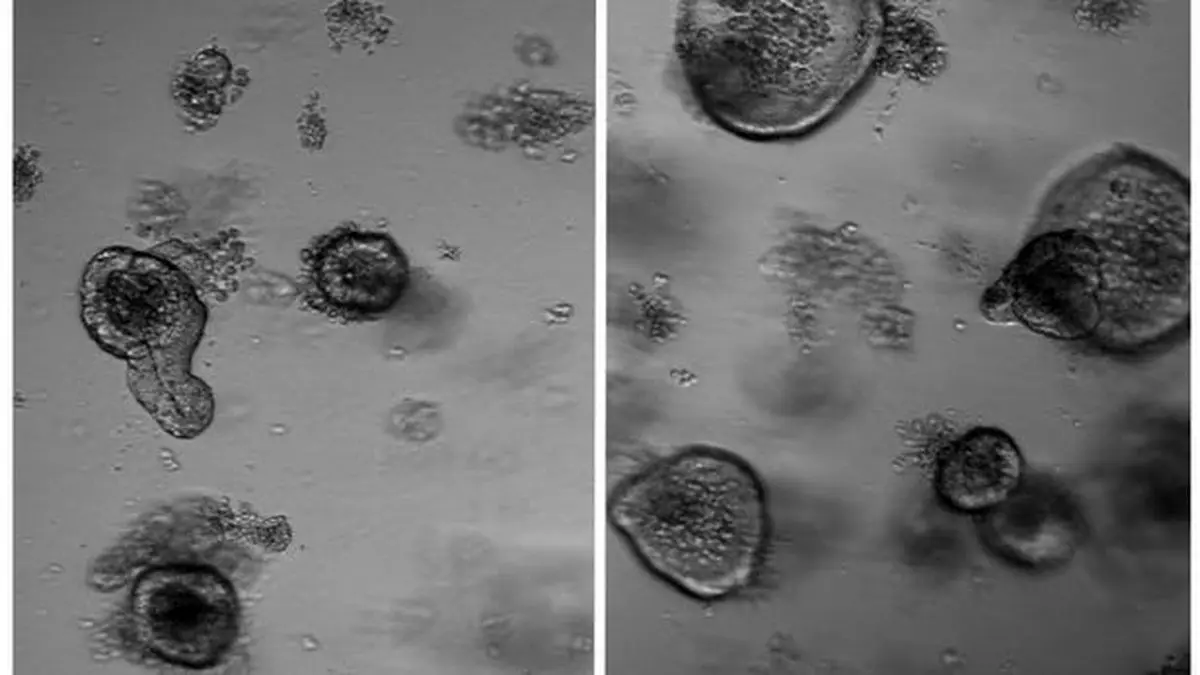

سپس نمونه‌هایی از سلول‌های بنیادی روده این حیوانات برداشتند و آنها را در ظرف کشت، رشد دادند. جایی که آنها به ارگانوئید(organoid) یا "مینی روده" رشد کردند.

محققان دریافتند که سلول‌های بنیادی روده موش‌هایی که چیزی نخورده بودند، رشد بیشتری دارد. تا آنجا که سلول‌های بنیادی آنها در مقایسه با گروه شاهد که به اندازه معمول غذا خورده بودند، توانایی دو برابری در بازسازی داشتند.

"ماریا میهایلووا" از محققان این مطالعه می‌گوید: بسیار واضح بود که روزه‌داری تاثیر بسیار زیادی بر روی توانایی کپسول‌های روده برای تشکیل ارگانوئیدهای بیشتر که سلول بنیادی محور است، دارد. این چیزی بود که ما هم در موش‌های جوان و هم در موش‌های سالخورده دیدیم و ما واقعا کنجکاو شده‌ایم که بدانیم سازوکار مولکولی این فرآیند چیست؟